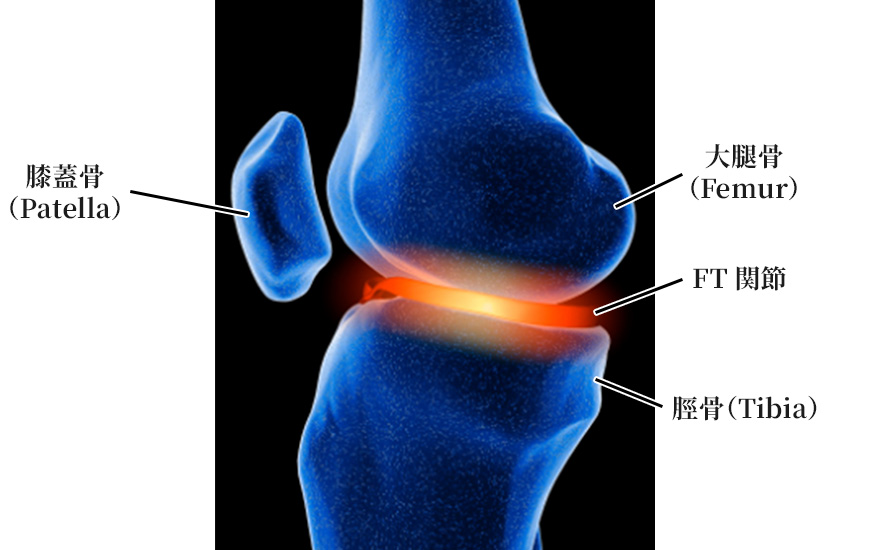

膝は大腿骨、脛骨、膝蓋骨がそれぞれ関節を形成しています。

つまり大腿骨-脛骨との関節と、膝蓋骨-大腿骨との関節です。関節を構成している関節軟骨は加齢や外傷により環境変化を生じて削れて痛みを伴っていきます。